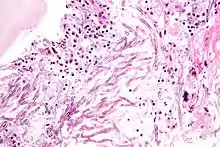

Cryptococcus neoformans puede causar una forma grave de meningitis y meningoencefalitis en pacientes con infección por VIH y SIDA . La mayoría de las especies de Cryptococcus viven en el suelo y no causan enfermedades en los seres humanos. Cryptococcus neoformans es el principal patógeno humano y animal. Este hongo no presenta ergosterol en su membrana. Se sabe que Cryptococcus laurentii y Cryptococcus albidus ocasionalmente causan enfermedad de moderada a grave en pacientes humanos con inmunidad comprometida. Cryptococcus gattii es endémico de las partes tropicales del continente de África y Australia y puede causar enfermedades en personas no inmunodeprimidas.[2]

Las células infectadas de C. neoformans suelen ser fagocitadas por macrófagos alveolares en el pulmón.[6] Las células invasoras de C. neoformans pueden morir por la liberación de moléculas oxidativas y nitrosativas por estos macrófagos.[7] Sin embargo, algunas células de C. neoformans pueden sobrevivir dentro de los macrófagos. La capacidad del patógeno para sobrevivir dentro de los macrófagos probablemente determina la latencia de la enfermedad, la diseminación y la resistencia a los agentes antifúngicos. Para sobrevivir en el entorno intracelular hostil del macrófago, una de las respuestas de C. neoformans es regular positivamente los genes empleados en las respuestas al estrés oxidativo .